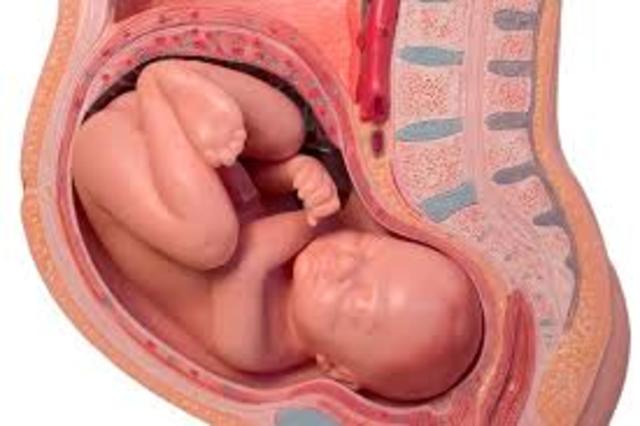

La mayoría de los órganos del bebé están prácticamente formados y sólo se dedica a ganar peso y talla. Aunque cada vez tiene menos espacio para poder moverse, su actividad no se detiene. Si a estas alturas del embarazo no está colocado boca abajo, es muy posible que comience a hacerlo a partir de esta semana.

En esta semana, el bebé puede medir 46 cm de longitud y pesar ya más de 2 kilos. Los huesos de su esqueleto están prácticamente endurecidos, a excepción de los de la cabeza. El hecho de que los huesos del cráneo sean más blandos y todavía no se hayan encajado facilita el paso del bebé por el canal de parto, el vérnix, una sustancia grasienta que recubre la piel del bebé, es cada vez más denso, facilita que el bebé atraviese la vagina en caso de que se produzca un parto vaginal.